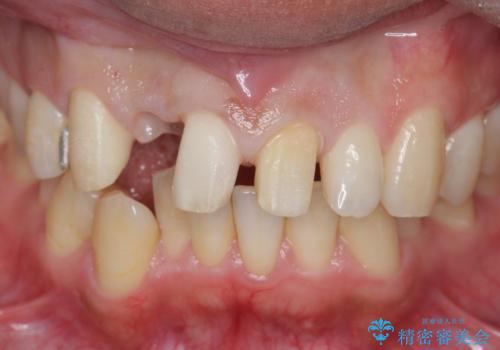

- 他院で右上の前歯の状態が悪いことを指摘されて来院。

昔ぶつけてしまった既往がありました。

歯の根の部分が内部で吸収し、周りの骨も吸収してしまっていました。

このまま放置すると、骨の吸収も進行し、いずれ近い将来歯が折れてしまう可能性もありました。また、隣の歯にも骨の吸収による影響が始まっており、持たせるだけ持たせたとしても次のステップの時には状況が悪化してしまうことが予想されました。

以上を説明したところ、早めに抜歯を行いブリッジにしていくことを希望されたため治療開始しました。

右上2番の周りの歯槽骨がかなり吸収が進んでいた影響で、抜歯後そこが大きくへこむことが予想されました。

抜歯後即時にバイオスを詰めることで抜歯後の骨の吸収をなるべく抑える治療(ソケットプリザベーション)を行いました。

歯槽骨が吸収してしまった右上1(隣の歯)との境界については右上1番遠心の歯周ポケットが深いことについては解決できない為、いずれまたダミーの歯の部分に関しては歯肉が下がってしまうことについては説明済みです。

ただ、年齢も鑑みて、直ちに右上12抜歯ではなく、まずは2番のみの抜歯でブリッジにする処置を行いました。